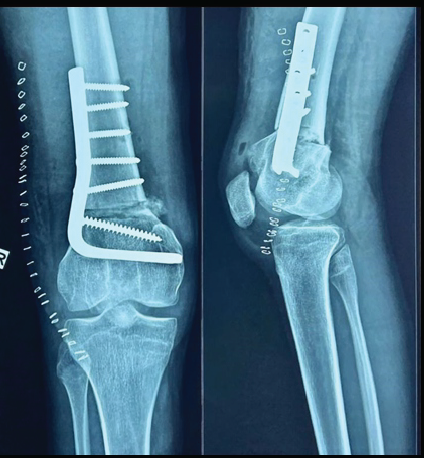

Under general anesthesia, under pneumatic tourniquet control, the distal femur was exposed through a lateral approach. A 90° fixed-angle AO blade plate was chosen for fixing the osteotomized femur. A pin was inserted just proximal to the physeal scar at the planned osteotomy site so that the blade of the blade plate and one screw could be used distal to the osteotomy site for fixation. The path for the blade portion of the blade plate was prepared distal to the planned osteotomy site before starting the osteotomy, such that the blade of the blade plate lies parallel to the proximal tibial plateau (Fig. 5) and forms an angle with the femoral shaft proximally, which indicates the amount of correction needed.

Figure 5: Osteotomy of distal femur

The distal osteotomy is performed first by marking the osteotomy site 15 mm proximal to the blade such that it is also in parallel with the proximal tibial plateau (Fig. 5). The proximal osteotomy is marked in such a way that the osteotomy is perpendicular to the proximal femoral shaft (Fig. 5). Both the osteotomies are performed with the tip of the wedge ending posteriorly (Fig. 5). The bone is then removed and the distal portion is extended and fixed to the proximal portion with the blade plate and appropriate screws – blade and one cancellous screw distally and four 4.5 mm cortical screws proximally (Fig. 6).

Figure 6: Correction of Fixed flexion deformity